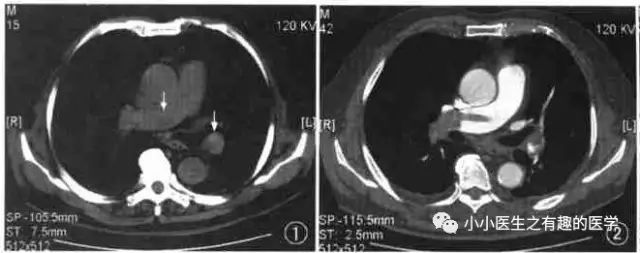

仔细看,有端倪。

增强CT可以核实。

很明显,患者做了CT平扫,我们要仔细阅片,发现可疑,及时增强CT,要不然就漏诊了。